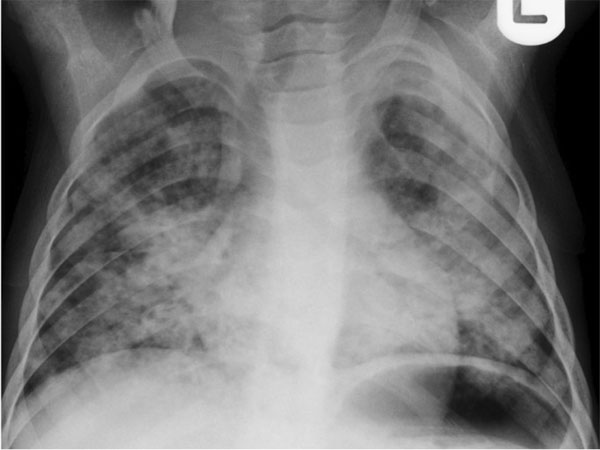

New Delhi, Oct 28: Routine chest X-rays, commonly used to screen for tuberculosis (TB), are failing to detect a large number of asymptomatic cases, according to a new study published in The Lancet Global Health.

Researchers from the University of Cape Town, South Africa, found that standard chest radiographs — even when used alongside symptom-based screening — missed more than 40% of TB cases among people who showed no symptoms but lived with patients diagnosed with pulmonary TB.

The study screened 979 household contacts of TB patients in three South African communities using universal sputum microbiological testing, which served as the reference standard. Pulmonary TB was confirmed in 5.2% of participants, but 82.4% of these individuals had no symp